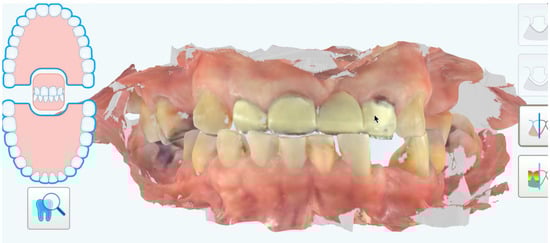

A 48-year-old female patient presented to the clinic with the chief complaint, “I need some dental work, and I do not like to wear my removable denture.” After clinical evaluation, the patient was diagnosed with missing teeth (numbering using the universal tooth numbering system) #1, 4, 5, 9, 12, 14, 15, 16, 17, 19, 20, 30, and 32; spaces between teeth #6 to 7, and #23 and 22; a fixed dental prosthesis (FDP) from #7 to 10 with the pontic on #8; an ill-fitting maxillary cobalt-chromium removable partial denture; generalized incisal and occlusal wear for all present dentition; and torus palatinus. The patient had some loss of vertical dimension of occlusion (VDO). The patient was offered an FMR, including some implants in the edentulous areas; however, the patient rejected any surgical treatment and elected the FMR option with tooth-supported prostheses. An initial digital scan (iTero Element 5D, Align Technology, Inc, San Jose, CA, USA) was captured. The centric relation (CR) was registered with an increased VDO of 3 mm using vinyl polysiloxane (VPS) material (Regisil Rigid Bite Registration Material, Dentsply Sirona, Charlotte, NC, USA) after manual manipulation to the centric relation position (Figure 1).

Figure 1. Initial intraoral scan.